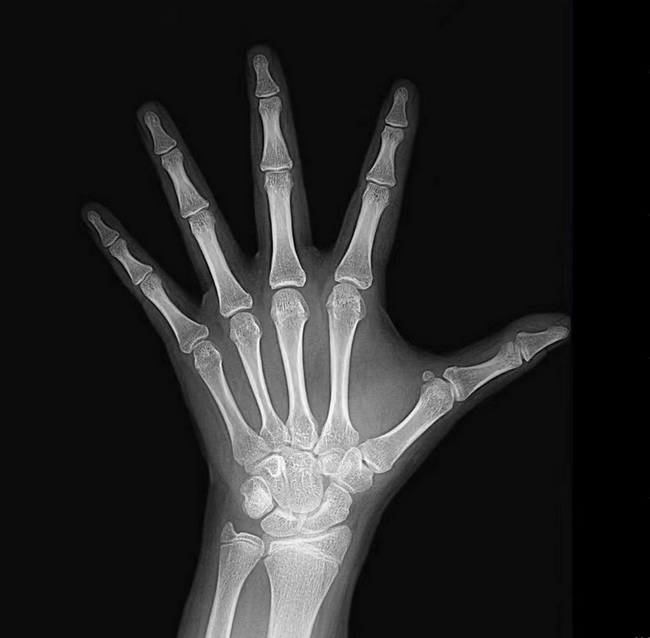

人体在发育过程中,骨骼形态及干骺端闭合时呈现一定的规律性,该规律以时间表示即为骨龄,骨龄即骨骼年龄,骨龄是个体成熟度的生物学标记之一,其与身高增长速度、初潮年龄、肌肉质量和骨矿物质质量等参数的相关性优于生理年龄,比生物学年龄更能反映个体的成熟度。因此骨龄广泛应用于生长发育监测以及多种儿童内分泌疾病的筛查、诊断、疗效评估。临床中我们常将骨龄用于成年身高预测。